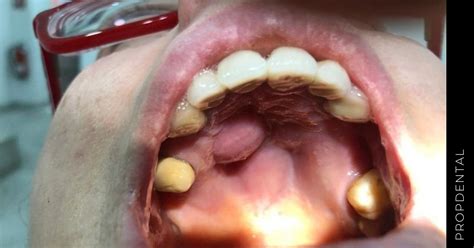

Un bulto en el paladar puede ser una experiencia inquietante. Esta área, fundamental en la cavidad bucal, puede sufrir infecciones o presentar afecciones, como la aparición de algún bulto. A menudo centramos nuestra atención en las piezas dentales y encías, sin embargo, la cavidad oral requiere la misma atención y cuidados. La señal para saber si nuestro paladar goza de buena salud es fijarnos en que tenga un color rosáceo uniforme. Si descubrimos irritaciones, bultos o inflamación general, pueden ser indicativos de padecer algún tipo de enfermedad bucodental.

Tener un conocimiento sobre este tipo de trastornos nos puede permitir una detección más rápida y poder acudir a nuestras consultas con mayor información previa que puede ayudar, seguramente, a mejorar tu salud dental en caso de ser un problema considerable. Un bulto en el paladar es una protuberancia o masa que aparece en la parte superior de la boca. Estos bultos pueden tener distintos tamaños, formas y consistencia diferentes, y pueden ser tanto blandos o duros si los presionamos.